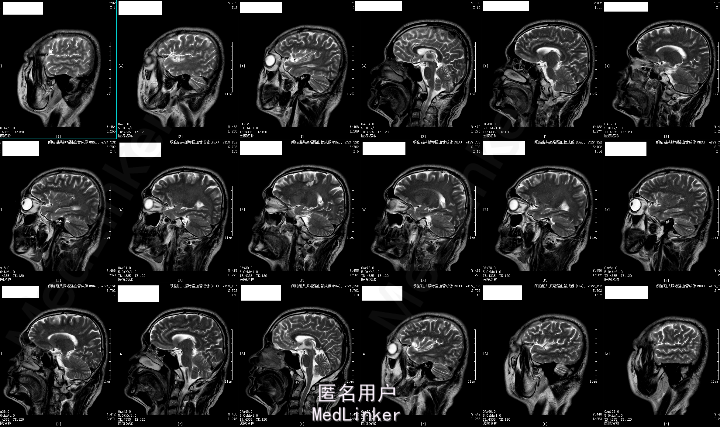

2015-05-26外院头颅MR:1.左额叶、枕叶病变考虑感染性病变可能性大(曼氏裂头蚴感染?)2.双侧上颌窦、筛窦慢性炎症。

2015-6-01我院头颅MRA:1.左侧额叶、枕叶及左侧基底节尾状核多发异常信号,考虑寄生虫感染(曼氏裂头蚴感染?)可能性大;2.左侧大脑前动脉A1段起始部稍狭窄;3.双侧筛窦炎症。

患者今年4月份时有吃“田螺、黄鳝”病史,既往有“高血压、糖尿病”,未规律治疗,结合其临床表现及头颅MRA“钻隧道”样改变,目前考虑“曼氏裂头蚴感染”可能性大。

成的中枢神经系统寄生虫病。I临床较为少见,易误诊。一般认为感染该病的途径有以下几种:食生或半生的蛙肉、蛇肉等(含裂头蚴);带有伤口的皮肤敷贴感染的生蛙皮、蛙肉等;饮用了含剑水蚤的生水。脑裂头蚴病的临床表现因感染部位的不同而各异。多以头痛、癫痫大发作及肢体活动障碍等为主,严重者可致颅内高压、视力损害、意识障碍甚至突然死亡。脑脊液检查可有蛋白及细胞数轻度升高。儿童脑裂头蚴病的病程一般不长,有些因虫体的迁延,其症状和体征也会发生改变。该病影像学表现多为单侧受累的单发病灶。病灶多位于皮质,也可侵犯脑室、脑干和小脑。活的虫体在脑内活动形成隧道、虫体分泌的产物及虫道周围的炎性反应使得该病影像学上具有一定特点:(1)主病灶一般较小,直径小于2 cm;(2)局部常伴发炎性反应,病灶周围脑实质可见不规则大片状水肿影;(3)MRI检查多表现为混杂长T1、长T2信号,临近侧脑室可变大,即所谓的“负效应”,增强扫描可见病灶呈匍行管状、串珠状、绳结状、扭曲条索状强化;(4)不同时期的影像学检查,病灶可在不同的部位;(5)CT检查可见点状钙化影,虽脑MRI对于钙化的显影不如CT,但也可表现出不均匀信号。脑裂头蚴病的病理学表现具有一定特点,裂头蚴幼虫在脑内迁徙游走形成坏死隧道,同时释放蛋白酶毒素溶解周围组织引起炎性反应,周围脑组织坏死后,局部炎性细胞浸润和纤维胶质细胞增生形成炎性肉芽肿。肉芽肿内可见有一条或数条虫体,虫体不分节,实体、无体腔,具有特征性的体壁结构是散在分布的椭圆形石灰小体及束状纵行肌纤维,前者可能为虫体的残骸。裂头蚴抗体血清免疫学检查(ELISA法)具有高度的特异性和敏感性。手术摘除裂头蚴为该病最有效的治疗手段,可